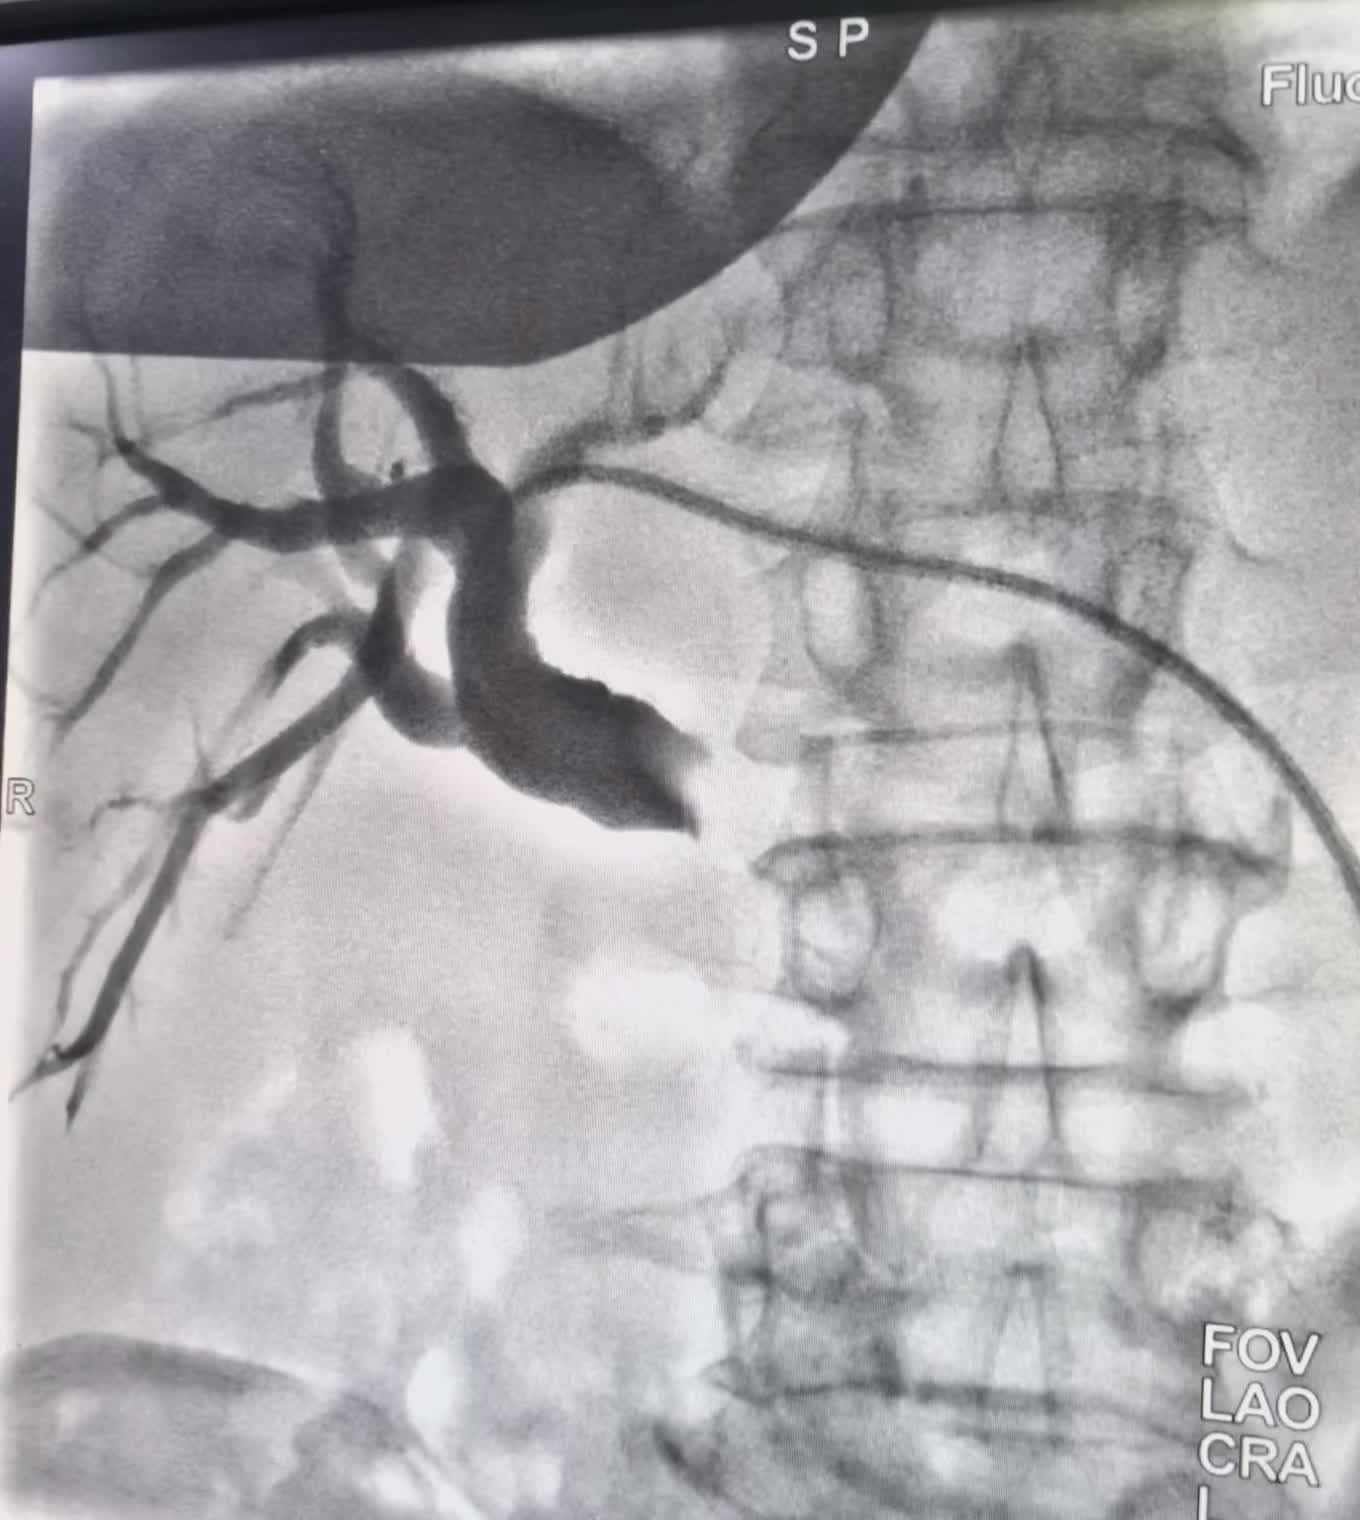

上周做的一例贲门癌老年患者,对静脉化疗病变不敏感,化疗后恶心呕吐无力症状重,而切病灶有进展增大。患者拒绝在次静脉化疗。家属了解了可以通过动脉入路超选择直达供肿瘤动脉,灌注化疗栓塞术。化疗药物用量小,浓度大,做用强而切可以阻断肿瘤供血。一个小针眼,局麻下进行,术后反应不明显。疗效确切,患者易接受!希望有一个好的疗效!